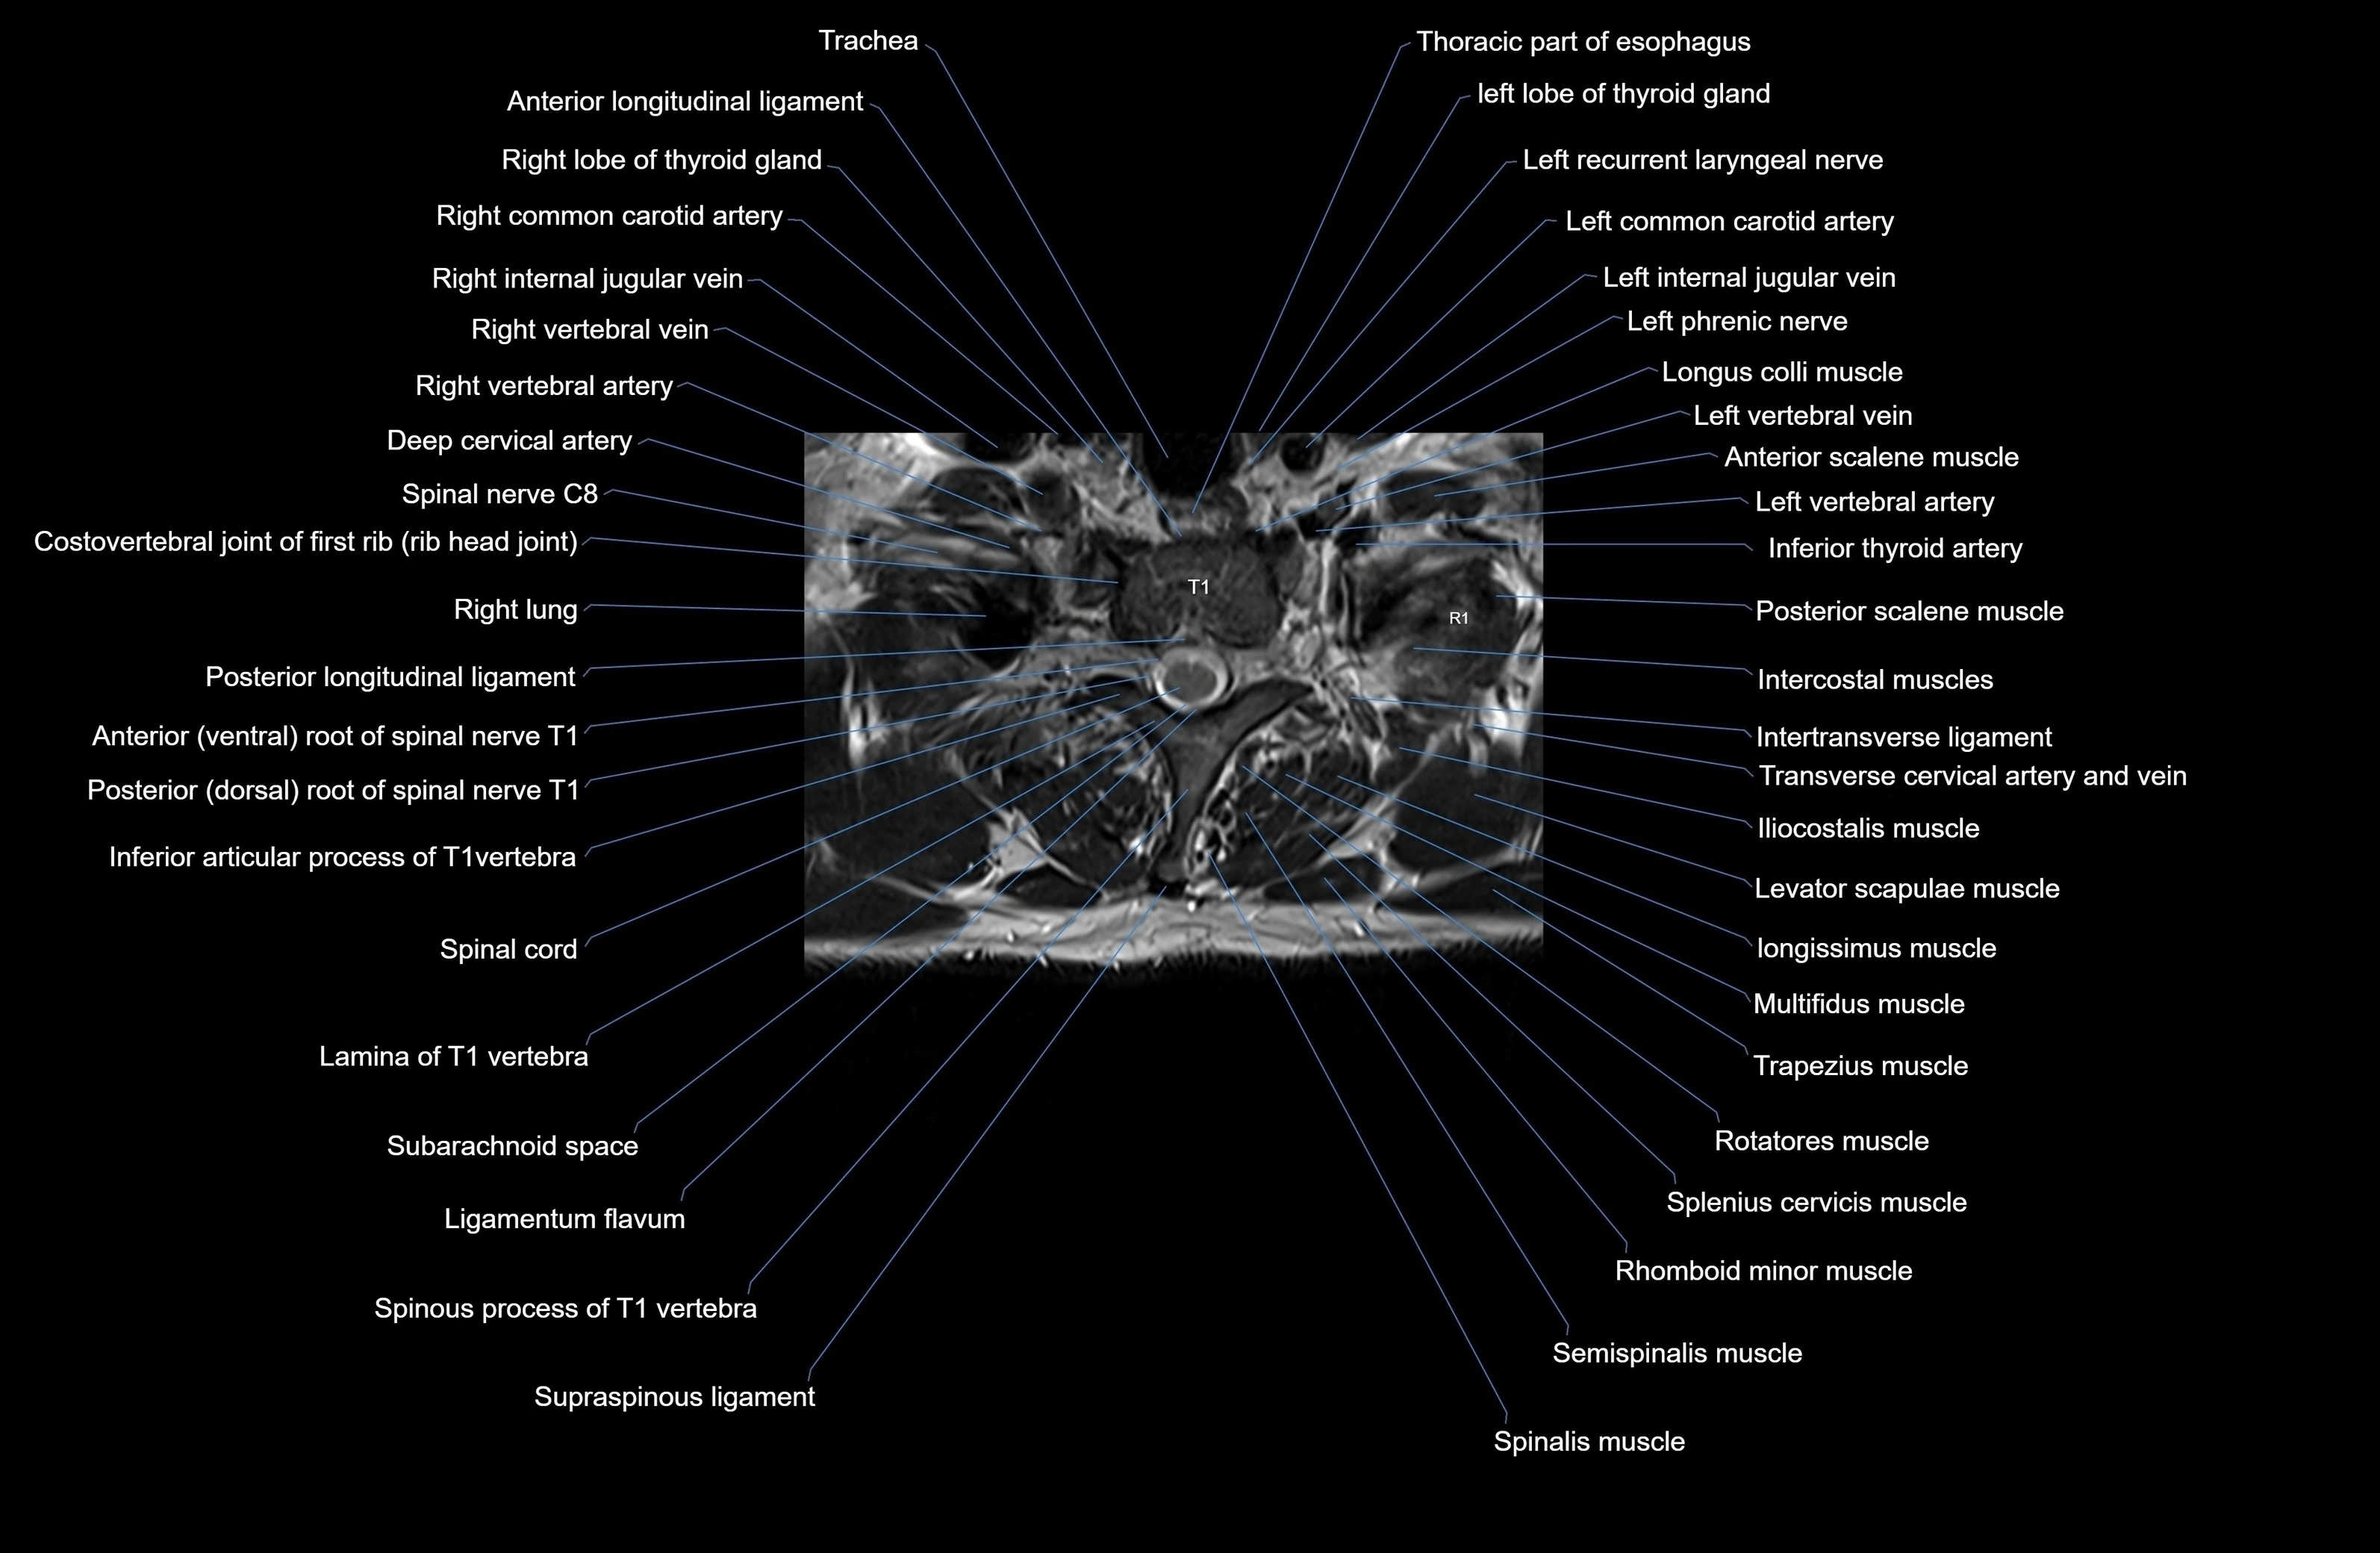

MRI image

image